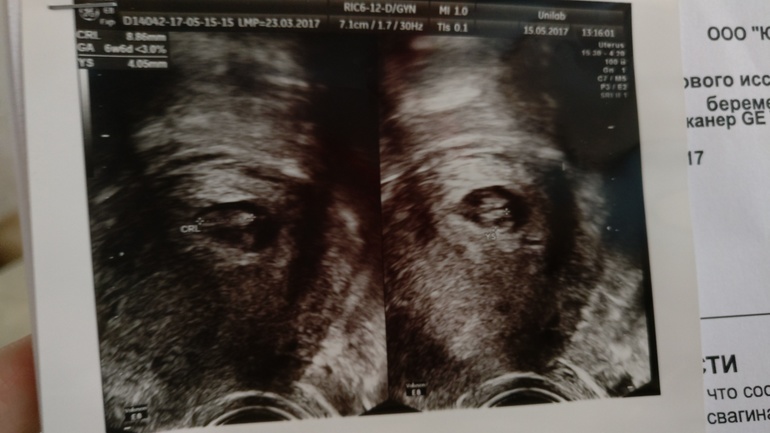

Узи в 7нед.4дня. Эмбриону мало места

И так, результаты Узи.

ПЯ - 12 мм ( на 5-6 нед)

Эмбрион - 8мм (6 нед,6дней)

ЧСС - 131 уд/мин

В заключении поставили срок 6-7 недель. Гипоплазия матки, гипоплазия хориальной полости (экзоцелома) .

К слову, была на узи в 5 недель, ПЯ был 7мм. За 2 недели ПЯ выросло всего на 5 мм...

У эмбриончика всего 4мм свободного пространства, переживаю очень, беременность очень долгожданная и желанная. Есть ли такие у кого ПЯ и ребеночек выровнялись и всё хорошо? Знаю, что если ПЯ отстанет в развитии то эмбриону просто некуда будет расти и Б прервется. Очень хочется верить в чудо!!